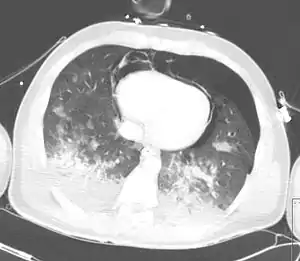

Computed tomography

A chest CT scan revealing pulmonary contusions, pneumothorax, and pseudocysts

Computed tomography (CT scanning) is a more sensitive test for pulmonary contusion,[6][33] and it can identify abdominal, chest, or other injuries that accompany the contusion.[38] In one study, chest X-ray detected pulmonary contusions in 16.3% of people with serious blunt trauma, while CT detected them in 31.2% of the same people.[45] Unlike X-ray, CT scanning can detect the contusion almost immediately after the injury.[43] However, in both X-ray and CT a contusion may become more visible over the first 24–48 hours after trauma as bleeding and edema into lung tissues progress.[46] CT scanning also helps determine the size of a contusion, which is useful in determining whether a patient needs mechanical ventilation; a larger volume of contused lung on CT scan is associated with an increased likelihood that ventilation will be needed.[43] CT scans also help differentiate between contusion and pulmonary hematoma, which may be difficult to tell apart otherwise.[47] However, pulmonary contusions that are visible on CT but not chest X-ray are usually not severe enough to affect outcome or treatment.[37]